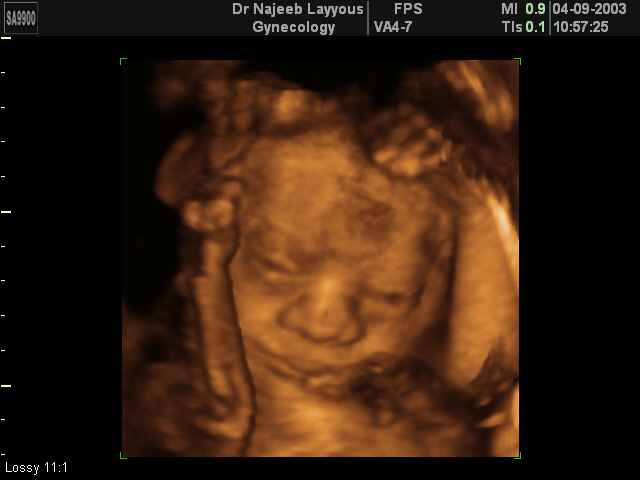

3D Fetal Face Ultrasound Scan Photos